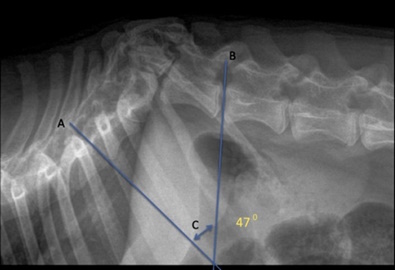

Ο βαθμός κυρτότητας της ΣΣ που συνοδεύει τον ή τους σπονδύλους με παραμόρφωση υπολογίζεται μετρώντας τη γωνία Cobb. Η γωνία Cobb προκύπτει από τη διχοτόμηση δύο γραμμών: η μια διέρχεται από τη πρόσθια πλευρά του τμήματος με τη κύφωση και η άλλη από την οπίσθια. Σύμφωνα με μια μελέτη οι περισσότεροι σκύλοι με νευρολογική δυσλειτουργία είχαν γωνία Cobb μεγαλύτερη από 350. Οι απλές ακτινογραφίες δίνουν πληροφορίες για την παραμόρφωση των σπονδύλων αλλά δεν δίνουν πληροφορίες για τη συμπίεση του ΝΜ ή για την παρουσία άλλων αλλοιώσεων (πχ συριγγομυελία, αραχνοειδής κύστη). Η MRI αποτελεί την απεικονιστική μέθοδο επιλογής διότι δίνει πληροφορίες που αφορούν το παρέγχυμα του ΝΜ.

Γωνία Cobb 470